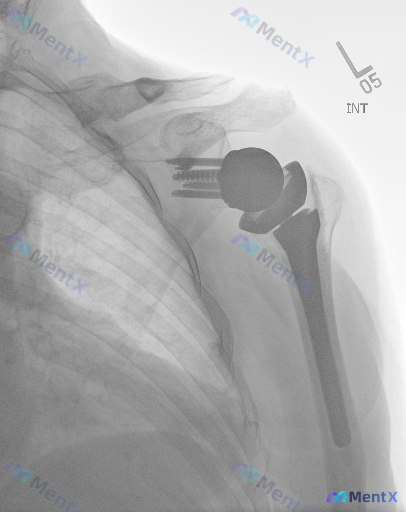

这张左肩关节置换术后的X光看起来很"干净",真的没问题吗?

整理了一份左肩关节反式置换术后的X光正位片资料,影像科的直接结论是“假体位置良好,未见明确的形态学异常(如假体移位、急性骨折、明显的骨溶解或软组织肿胀)”。

但这份分析报告后面的部分很有意思——它特别强调了“影像学的静态完美”与“临床功能的动态不确定性”之间的分离,还把“亚临床假体周围感染”列为了最大的临床盲区。